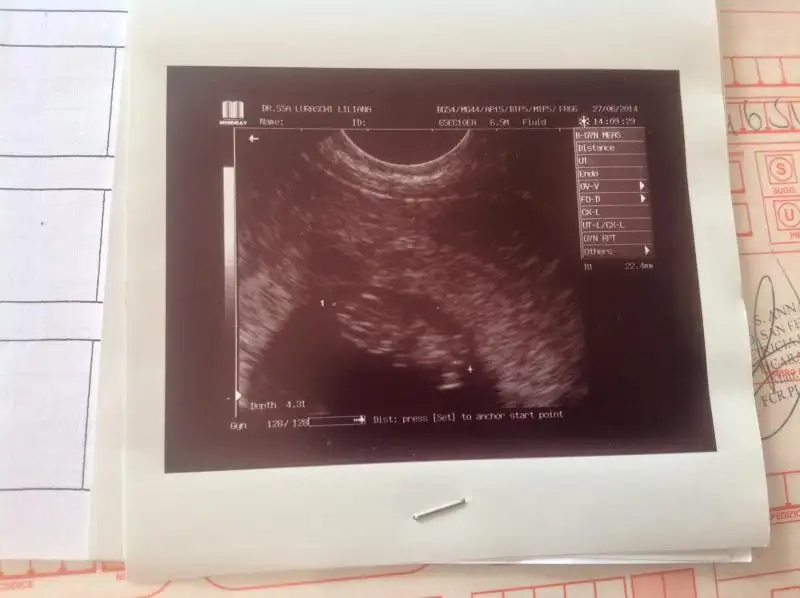

Benim bebişimin sağ altta daha yolk kesesi duruyor ölçü alınan yer bebiş sadece :) bebek yolk kesesinin solunda duruyo ama ay bilemedim benim de en baştan beri içime kız doğuyor bakalım dışıma da kız mı doğcak 😀